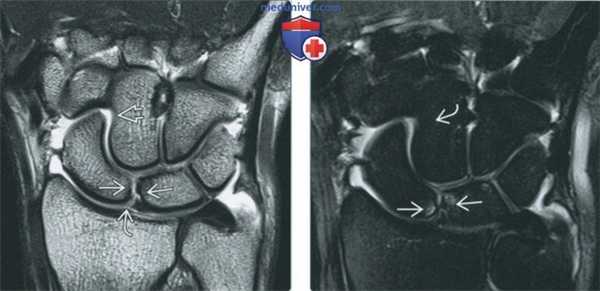

(Слева) МР-артрография в режиме PD FS, сагиттальный срез на уровне полулунной кости: определяются утолщенные луче-трехгранная и тыльная межзапястная в связки, которые имеют аморфную структуру с наличием прослоек жидкости между волокнами. Такая картина характерна для растяжения связок тыла запястья.

(Справа) МР-артрография в режиме PD FS, аксиальный срез через середину запястья, этот же пациент: визуализируются утолщенные связки, которые характеризуются гетерогенной структурой.